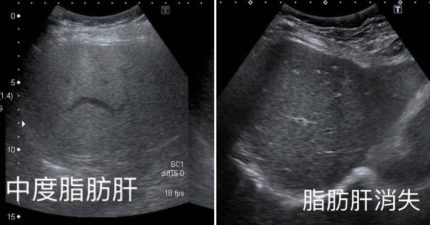

她「少吃1物」中度脂肪肝消失 醫追問驚:一年瘦了快10公斤